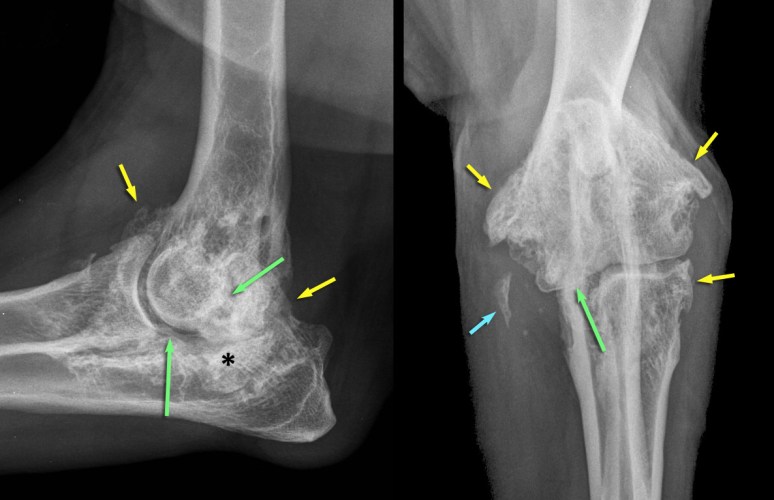

On note d’abord une prolifération osseuse périarticulaire marquée (flèches jaunes), dont le contour est irrégulier mais bien défini, indiquant un processus inactif à faiblement actif. Cette prolifération est compatible avec une ostéophytose (i.e. aux marges articulaires, à la jonction synoviale/capsulaire) et/ou enthésophytose (i.e. à l’intérieur des tissus mous périarticulaires, au site d’insertion dans l’os = enthèse). Quelques foyers minéraux amorphes sont situés médialement au coude (flèche bleue), impliquant probablement le ou les tendons fléchisseurs du coude s’insérant sur l’épicondyle huméral médial situé plus haut. Les marges sous-chondrales (flèches vertes) sont irrégulières et l’espace articulaire est hétérogène par endroit (notamment sous le processus anconé). Une incongruence articulaire est suspectée, alors que le processus coronoïde latéral est plus haut que la tête radiale sur la vue latérale (flèche verte) et que le processus coronoïde médial est mal défini et semble plus haut que la tête radiale sur la vue cranio-caudale (flèche verte). Finalement, on note une sclérose (*) sous-chondrale à l’incisure ulnaire. Ces changements sont compatibles avec de l’ostéoarthrose sévère, vraisemblablement secondaire à une dysplasie du coude (incongruence et fragmentation du processus coronoïde médial). Les marges articulaires ne montraient pas de lyse sous-chondrales, ce qui aurait permis de suspecter une arthrite rhumatoïde. Il n’a pas de lyse au site d’insertion de la capsule articulaire pour suggérer une tumeur agressive des tissus mous articulaires, ni de lyse médullaire ou corticale pour suggérer un ostéosarcome. Une arthrite septique aurait aussi engendré des changements mal définis (alors que la prolifération dans ce cas est bien définie) et une lyse sous-chondrale devrait être visible assez tôt dans le processus.